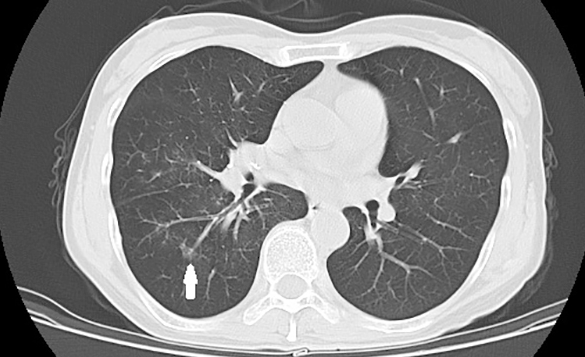

【垂医病例科普】胸外科:肺部磨玻璃结节…

2024-10-21